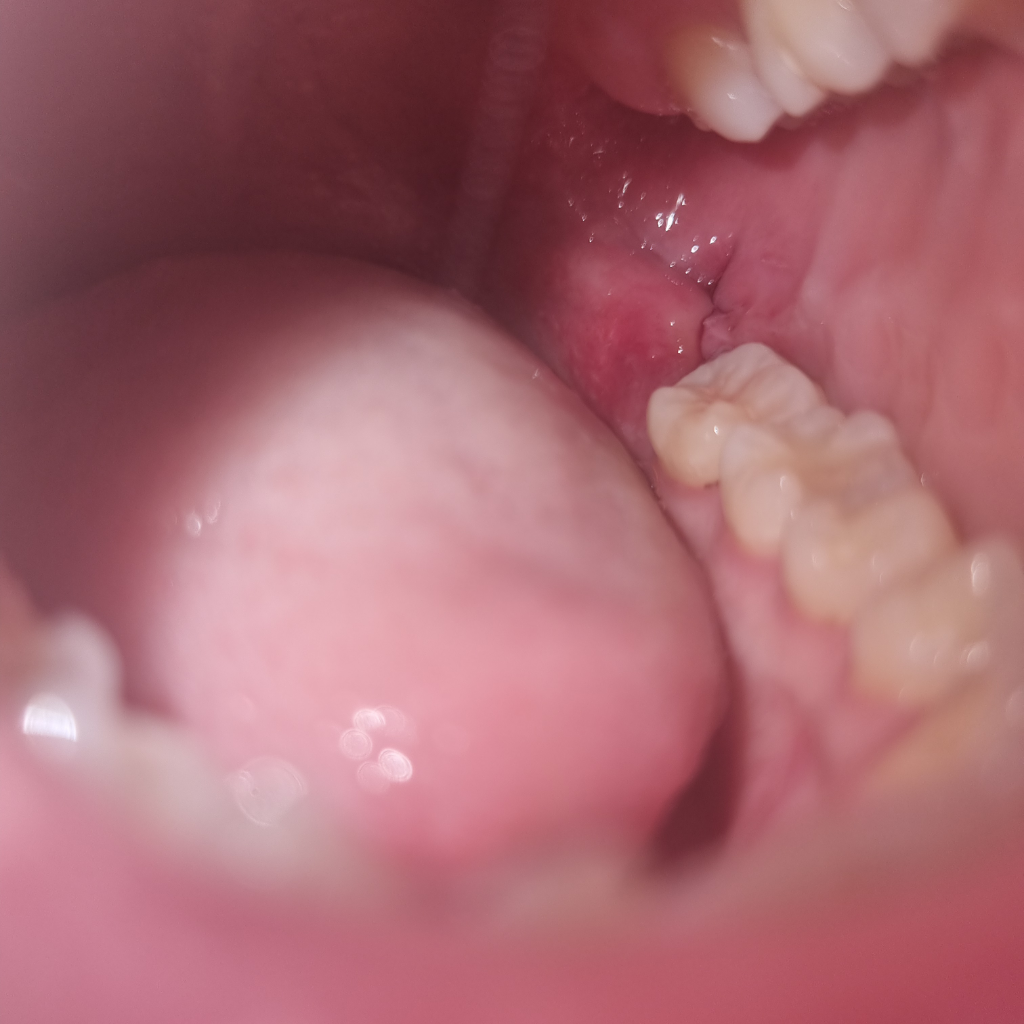

지난 금요일 10일 낮 12시에 하악 매복사랑니 발치완료후 6시간뒤에 지혈완료되었습니다. 거즈 뺄때 잠깐 봤는데 실밥도 피떡도 안보이길래 걱정하다가 오늘도 안보이는데 이런경우도 있나요?

사랑니 발치후 잇몸이 붓거나 하면 실밥이 보이지 않는 경우가 있습니다.

또한 실밥이 풀리거나 하는 경우에도 보이지않을수 있어요.

크게 문제가 되지는 않지만 출혈이 많이 되거나 걱정이 되신다면 치과에서 진료를 받아 보세요.

해당부위가 깔끔하고 병소가 없고 염증도 적어서 괜찮을 것으로 보입니다.

3일 뒤에 소독한번 가시고 1주일 뒤에 실밥 빼시러 한번 치과 들르시면 되시겠습니다.

실밥이 저절로 풀리기도 합니다. 사진상으로는 전혀 문제없이 잘 낫고 있는것으로 보입니다